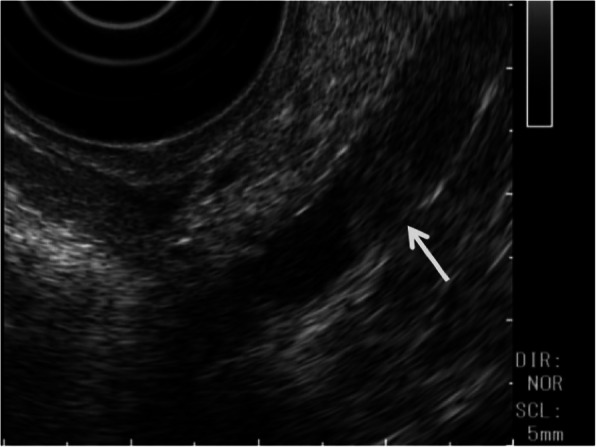

Abdominal contrast-enhanced computed tomography (CT) showed a slightly dilated CBD and a high-density spot in the DBD, suggesting a CBD stone (Fig. 1). Endoscopic ultrasonography demonstrated an elevated lesion on the DBD (Fig. 2). Permeation to the pancreatic parenchyma or to the outside of the bile duct wall was unclear. Endoscopic retrograde cholangiopancreatography (ERCP) revealed a circumferential stenosis 11.8 mm distal from the ampulla of Vater and a 5.1 × 6.5 mm irregularly shaped, elevated lesion on the DBD (Fig. 3). A double pig-tail catheter (7 Fr, 6 cm) was inserted in the bile duct. Brush cytology showed atypical ductal cells, indicating adenocarcinoma (AC) of the DBD.